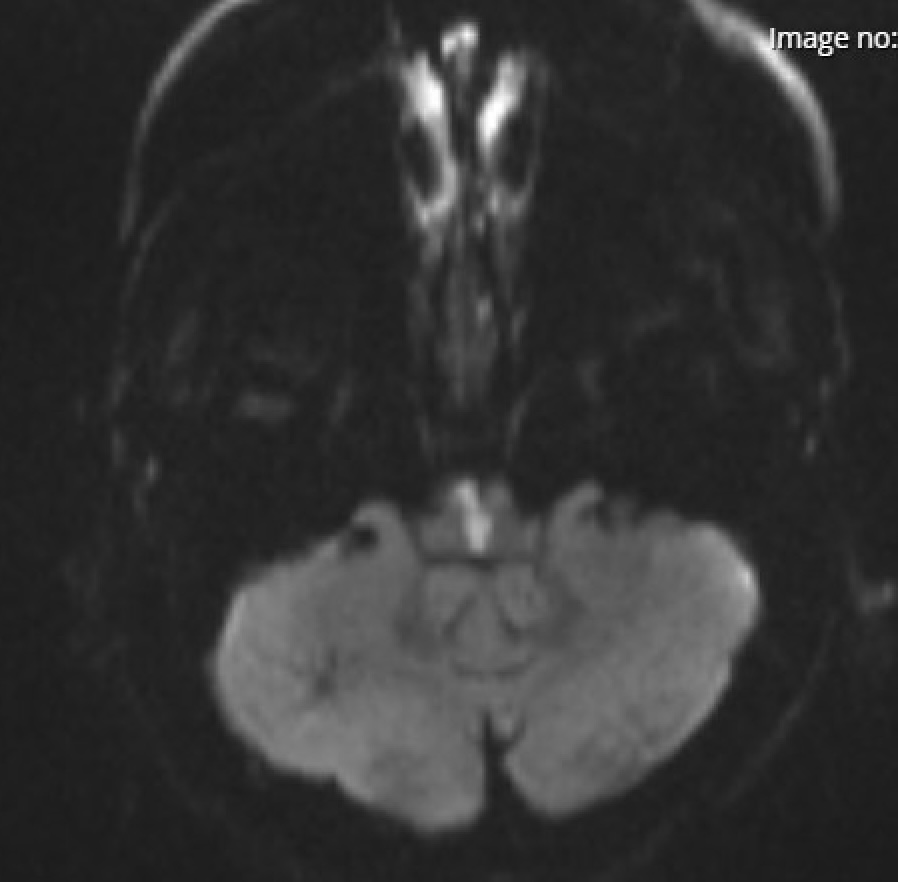

MRI provides high-resolution images using magnetic fields and radiofrequency pulses, making it the modality of choice for most neurological diseases.

Key Sequences:

T1-weighted: anatomy, structural detail, post-contrast imaging

T2-weighted: edema, inflammation, and demyelination

FLAIR: suppresses CSF to highlight periventricular lesions (e.g., MS)

DWI/ADC: detects acute ischemia

SWI: sensitive to blood products and calcification